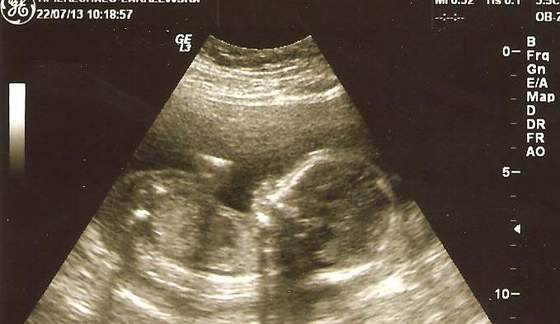

K-M.B- hehe super zdjęcie. To on się na nim rozkraczył, czy ja dobrze widzę?

powiem Wam, że ja podziwiam tych lekarzy - ja nie wiem jak oni na tym etapie widzą cipeczki i siusiaki

dla mnie czytanie rtg jest trudne a usg to juz w ogole czarna magia, ale dla nich to chleb powszedni